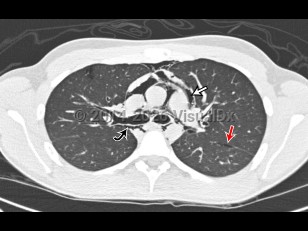

Pneumomediastinum in Adult

Pneumomediastinum is the presence of air in the mediastinum. It is caused by injury, most often esophageal or intestinal perforation. It is also seen as a result of aggressive bag-valve mask ventilation during resuscitation and intubation as well as a result of barotrauma in intubated patients.

Pneumomediastinum in Adult